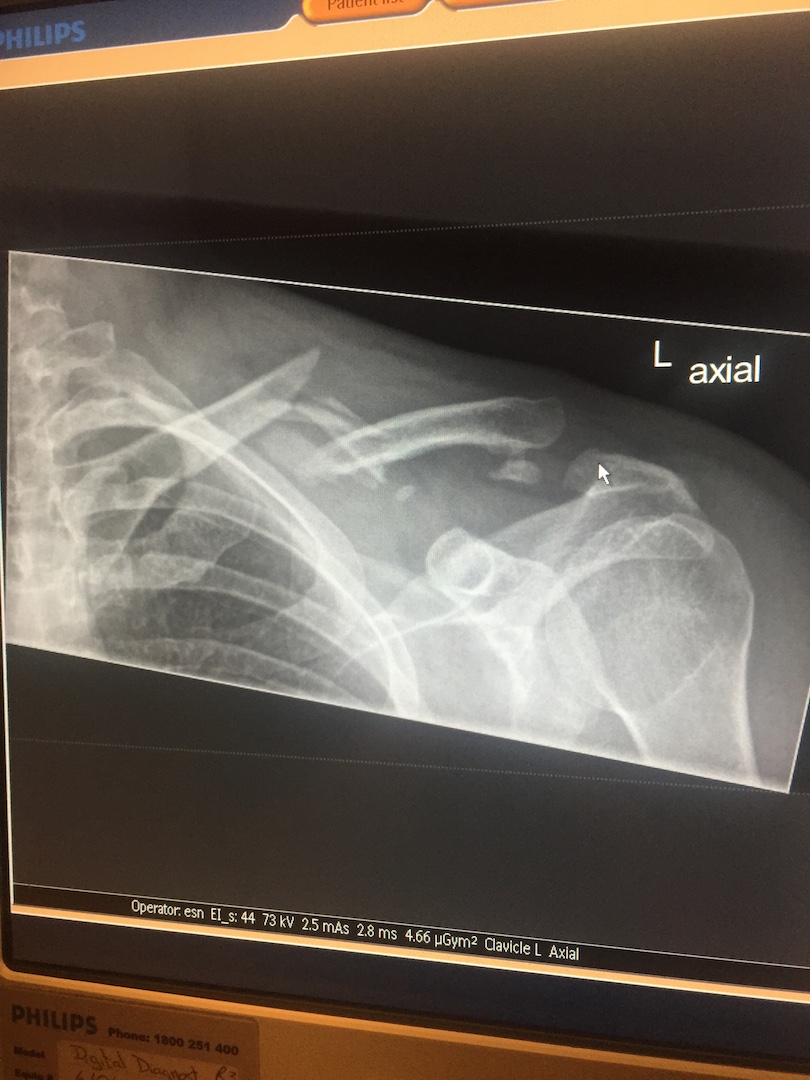

– If I may add a fourth . .  It was crashing on the Gibb River Road and not knowing if I would survive the day out. Me lying on the side of one of the most remote areas in the world, run out of water and surrounded by the pieces of my bike scattered all over. But I managed, with some help of friend to get the bike up, to strap it together and ride it to a cattle ranch 20 clicks down the road, with a badly broken shoulder and bruised ribs and concussion, it was challenging.  I was air lifted to Broome after some great treatment at the cattle station and my bike was brought down by a guy who worked at the station to Perth. What an awesome guy to do that, a week after I crashed I then learned that my grandmother had passed away in the UK so I had to fly home whilst I was in pretty bad shape physically for the funeral. Some homesickness had set in and it was quite a dark few weeks for me. But when I returned, I started on rebuilding the KTM and as soon as I had it up running and breathing fire again I had a new lease of life. And East I headed!